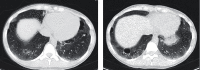

Interstitial lung disease (ILD) associated with connective tissue diseases (CTDs) is highly heterogeneous in its clinical presentation and course. The diagnosis and management of CTD-ILD require a multidisciplinary approach involving, at minimum, a rheumatologist, a pulmonologist, and a radiologist. Close monitoring of patients with CTD-ILD is important to enable early detection of disease progression and inform decisions regarding the initiation or escalation of pharmacotherapy. In the absence of guidelines regarding how CTD-ILDs should be treated, clinicians face difficult decisions on when to use immunosuppressant and anti-fibrotic therapies. The importance of a multidisciplinary and individualized approach to the diagnosis and management of CTD-ILD is highlighted in the three case studies that we describe in this article.